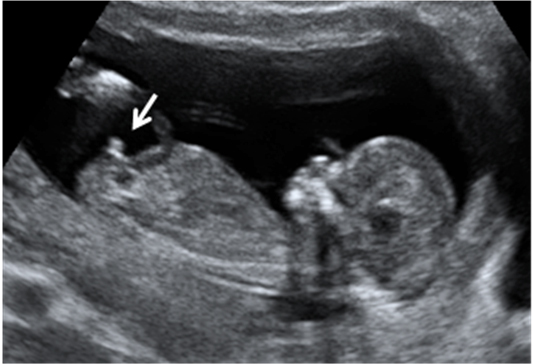

Ecografía Embarazo 2D y 3D Semana 12 - PRUEBAS DIAGNÓSTICAS